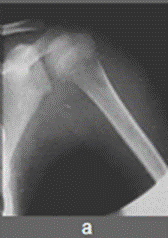

Кокковую остеомієліт. Гострий кокковую остеомієліт прийнято називати неспецифічним, хоча його можна впевнено розпізнати за допомогою рентгенологічного дослідження, клінічного перебігу і лабораторних даних, тобто на підставі властивих саме йому специфічних симптомів. Гостре початок, висока температура, важкий загальний стан, зміни формули крові, що свідчать про інфекційне захворювання, а потім і місцеві симптоми - локальні болі і хворобливість, підвищення місцевої температури і почервоніння шкіри, припухлість дозволяють запідозрити гнійний процес в скелеті. Уражаються зазвичай метафізи трубчастих кісток з тенденцією поширення запалення в сторону діафіза [8; 1; 13; 5; 9; 2]. Рентгенографія, виконана протягом першого тижня захворювання, що не виявляє будь-яких змін. Лише до кінця другого - початку третього тижня вдається виявити місцевий (локальний) остеопороз, ніжні периостальні нашарування, а іноді і один або кілька дрібних деструктивних вогнищ в метафізі кістки (мал.1а).

Рис.1. а) Початок кокковую остеомієліту. Неоднорідний місцевий остеопороз метафиза плечової кістки. б) Той же хворий через 1 місяць. Розпал остеомієліту.

Безліч вогнищ деструкції в метафізі плечової кістки, оточених дифузним остеосклерозом. Плечова кістка потовщена за рахунок масивних періостальних нашарувань. Намічаються ділянки кортикальних секвестрів. в) Той же хворий ще через 2 місяці. Шляхом масованого антибактеріального лікування (ін'єкції в сідничні області) процес призупинений і переведений в хронічний. Кость потовщена, різко склерозірована, на тлі остеосклероза видно множинні залишкові деструктивні вогнища.